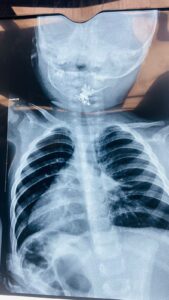

وأوضحت الطبيبة الاختصاص جراحة الأنف والأذن والحنجرة الدكتورة فرقان حميد محمد” أن الطفلة أُدخلت إلى صالة عمليات الطوارئ وهي تعاني من اختناق وسعال شديدين وعلى الفور تم إجراء الفحوصات والأشعة اللازمة التي أظهرت وجود جسم غريب في مدخل المجرى التنفسي.